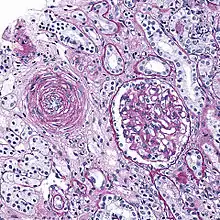

Hyaline arteriolosclerosis

Also arterial hyalinosis and arteriolar hyalinosis refers to thickening of the walls of arterioles by the deposits that appear as homogeneous pink hyaline material in routine staining.[3] It is a type of arteriolosclerosis, which refers to thickening of the arteriolar wall and is part of the ageing process.[4]

It is often seen in the context of kidney pathology.[4]: 284 In hypertension only the afferent arteriole is affected, while in diabetes mellitus, both the afferent and efferent arteriole are affected.

Lesions reflect leakage of plasma components across vascular endothelium and excessive extracellular matrix production by smooth muscle cells, usually secondary to hypertension.[7] Hyaline arteriolosclerosis is a major morphologic characteristic of benign nephrosclerosis, in which the arteriolar narrowing causes diffuse impairment of renal blood supply, with loss of nephrons.[5] The narrowing of the lumen can decrease renal blood flow and hence glomerular filtration rate leading to increased renin secretion and a perpetuating cycle with increasing blood pressure and decreasing kidney function.

Hyperplastic arteriolosclerosis

This is a type of arteriolosclerosis involving a narrowed lumen.[4] The term "onion-skin" is sometimes used to describe this form of blood vessel[8] with thickened concentric smooth muscle cell layer and thickened, duplicated basement membrane. In malignant hypertension these hyperplastic changes are often accompanied by fibrinoid necrosis of the arterial intima and media. These changes are most prominent in the kidney and can lead to ischemia and acute kidney failure.